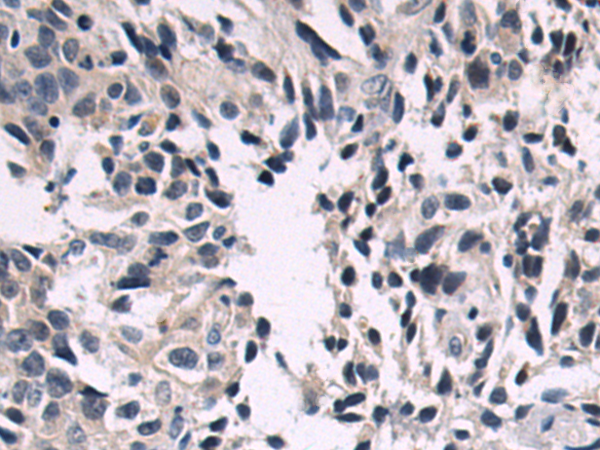

分类: 科研抗体货号: P10604别名: MCS; MOS; HMCS应用: IHC反应种属: Human